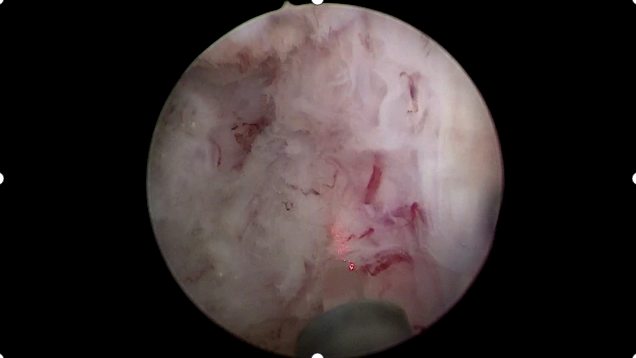

5月7日,贵州航天医院第60次晨读会由我院泌尿外科医师谢龙作学术交流,他以“负压吸引下软镜碎石取石术”为题,围绕输尿管软镜技术的临床应用与发展趋势,详细讲解了经尿道输尿管镜肾盂激光碎石取石术的操作要点及输尿管软镜技术的适应症与适用范围,并通过临床案例对比,重点阐述了经皮肾镜与输尿管软镜联合碎石术的协同优势,同时介绍了超微通道经皮肾镜联合输尿管软镜碎石术的技术创新点。针对临床疑难病例,分享了肾脏憩室内结石的处理策略、上尿路不明原因血尿的规范化排查流程,以及经皮肾镜术后残余结石的双镜联合处理方案。 泌尿外科专家简介 石 英 中共党员,泌尿外科党支部书记、负责人,主任医师 临床擅长:从事泌尿外科专业近30年,熟练掌握泌尿系各类疾病的诊治,具有丰富的临床经验,擅长泌尿系结石、腹膜后肿瘤及泌尿系肿瘤的手术治疗,对泌尿系感染、泌尿系结核、尿源性脓毒血症的救治有独到的见解及抢救经验。在贵州省率先引入输尿管软镜技术,同时在男科领域,对男性阳痿、早泄及前列腺疾病有很深的研究。 中国医师协会泌尿外科分会感染协作组委员,奥林巴斯泌尿系软镜西南区专家组成员,西南地区第一批输尿管软镜专家组成员,贵州省医学会泌尿外科分会委员,贵州省性学会理事,贵州省性学会常务委员,贵州省泌尿外科专业医疗质量控制中心专家委员会委员。 李国成 中共党员,泌尿外科副主任医师 临床擅长:从事泌尿外科及男科工作10余年,曾多次前往上海交通大学附属第一人民医院、中国中医科学院西苑医院进修学习男科;擅长性功能障碍的诊治、男性整形手术、前列腺增生激光手术、显微手术等。 中国人体健康科技促进会男科学专业委员会委员,贵州省性学会泌尿外科分会委员,贵州省医学会男科学分会委员,遵义市医学会男科学分会副主任委员兼秘书长,遵义市医学会泌尿外科分会常务委员,贵州航天医院男科带头人。 李 凯 中共党员,泌尿外科副主任医师 临床擅长:贵州航天医院肿瘤腔镜组带头人,擅长肾癌根治术、输尿管癌根治术、膀胱及前列腺癌根治术、腹腔镜输尿管狭窄切除吻合术、输尿管切开取石术等手术,在遵义市率先开展泌尿系结核后膀胱挛缩全腹腔镜下膀胱扩大术。 贵州省医学会泌尿外科分会青年委员,遵义市医学会男科分会常务委员,遵义市医学会泌尿外科分会常务委员。 谢 龙 中共党员,泌尿外科主治医师 临床擅长:熟练掌握泌尿外科基本手术,特别擅长泌尿系结石手术,单独完成输尿管硬镜、软镜1000余台,经皮肾碎石200余台,2023年共开展手术541台,个人年平均手术量约400台,三、四级手术量日最高达6台。 曾前往华西医院进修学习系统结石治疗,对输尿管软镜碎石有了更深刻的认识和体会,拜师清华长庚医院泌尿外科胡卫国教授,极大提升了经皮肾超声碎石及结石的微创治疗能力;从业以来,荣获医院年度考核优秀等次4次。 泌尿外科简介 基本情况 贵州航天医院泌尿外科创建于20世纪60年代,经过几代人的努力,微创与内镜手术占比达90%以上,科室亚专业框架完善。是贵州省临床重点专科建设单位、北京清华长庚医院李建新教授团队诊疗及会诊中心、北京医学会尿路修复与重建诊疗及会诊中心、上海公济泌尿外科集团遵义中心、上海援黔专家李铮教授男科工作室、贵州省泌尿外科质量控制专家委员单位。 专科特色 (一)泌尿系结石内镜碎石技术 泌尿系结石微创治疗领域方面是贵州省首家引进科医人钬激光碎石技术科室,在遵义地区率先掌握输尿管硬镜、软性镜,经皮肾镜钬激光碎石技术。目前是北京清华长庚医院泌尿外科“手把手”经皮肾镜碎石技术培训基地、贵州省输尿管软镜培训基地。 1.负压吸引可弯曲软镜鞘电子软镜碎石术 2.标准与超微通道相结合的经皮肾镜碎石取石术 (二)微创腹腔镜技术 泌尿外科腹腔镜技术师承于浙江省人民医院、北京解放军总医院。目前采用经腹、经后腹双入路法的腹腔镜技术完成肾部分切除、肾切除、肾输尿管全长切除、肾盂输尿管成形、输尿管狭窄吻合、膀胱翻瓣等手术。在遵义地区率先掌握腹腔镜下膀胱癌根治术、腹腔镜下前列腺癌根治术。 (三)男科、盆底技术临床应用 遵义地区男科分会主委单位,是贵州省首家引进尿动力学检查并取得了全国资质认证科室,也是贵州省首家进行RigiScan检查的单位。在遵义地区率先掌握显微取精子技术以及显微镜下治疗精索静脉曲张、显微镜下输精管吻合、输精管附睾吻合技术。率先采用前列腺激光剜除术治疗前列腺增生症。在陆军军医大学西南医院泌尿外科主任沈文浩教授指导下,完成遵义市首例神经源性膀胱骶神经调节刺激器置入术。 诊疗范围 诊疗范围(除外肾移植、癌栓):泌尿系结石、泌尿系肿瘤、肾上腺疾病、肾积水、前列腺增生、男性生殖器功能障碍(精索静脉曲张、生殖道感染、输精管梗阻等)、盆底功能障碍性疾病(膀胱脱垂、排尿功能异常、尿失禁)、泌尿生殖系畸形。 泌尿外科拥有独立门诊治疗室、日间手术室、尿动力学检查室、精液分析检查室、男性勃起功能检查及治疗室、ESWL治疗室、结石分析检查室。 end